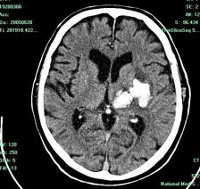

Современные методы нейровизуализации позволяют не только диагностировать внутримозговую гематому, но и выявить причину ее появления. Ведущим диагностическим методом является КТ головного мозга. Как правило, на томограммах внутримозговая гематома имеет вид очага гомогенной плотности округлой или овальной формы. Если гематома сформировалась в результате ушиба головного мозга, то она обычно имеет неровный контур. С течением времени происходит уменьшение плотности гематомы до изоплотного состояния, при котором ее плотность соответствует плотности мозговой ткани. Для малых гематом этот период составляет 2-3 недели, а для средних - до 5 недель. При уменьшении плотности гематома лучше визуализируется при помощи МРТ головного мозга, хотя в начальном периоде применение МРТ может привести к ошибочному диагнозу в пользу опухоли с кровоизлиянием. Поэтому, при наличие такой возможности, многие неврологи и нейрохирурги предпочитают использовать в ходе диагностики оба способа нейровизуализации (КТ и МРТ).

С целью выявления сосудистых нарушений, обусловленных рефлекторным ангиоспазмом, а также для диагностики аневризм и артерио-венозных мальформаций применяется ангиография головного мозга или магнитно-резонансная ангиография (МРА). Самостоятельно применяться в диагностике внутримозговой гематомы ангиография не может, поскольку не дает возможности точно отдифференцировать участок ушиба головного мозга от гематомы.